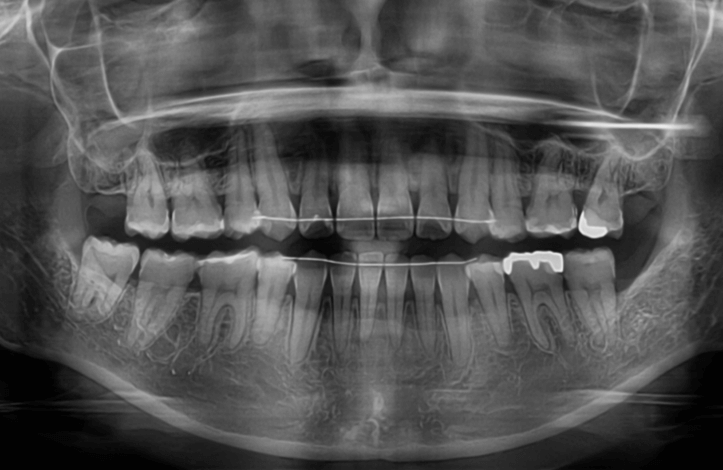

歯並び・かみ合わせ・口元の見た目が気になる

| 年齢・性別 | – |

|---|---|

| 主訴 | 歯並び・かみ合わせ・口元の見た目が気になるとの事でご相談があり矯正の治療を行いました。 |

| 治療期間・回数 | 2年 |

| 費用 | 1,001,000円 |